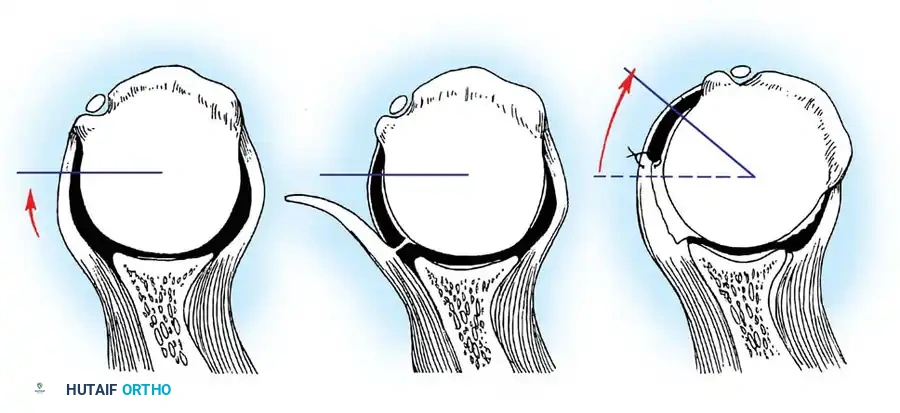

Bipolar Bone Loss

SURGICAL WARNING: Failure to recognize and address significant bipolar bone loss is the leading cause of recurrent instability following soft-tissue stabilization.

A Hill-Sachs lesion is an impaction fracture of the posterolateral humeral head, created when the head is driven against the hard anterior glenoid rim during dislocation. Burkhart and DeBeer introduced the concept of the "engaging" Hill-Sachs lesion, which levers the humeral head out of the joint when the arm is abducted and externally rotated.

Concurrently, anterior glenoid rim fractures or attritional bone loss can occur. Itoi demonstrated that a 20% loss of the anterior glenoid width critically compromises stability, rendering soft-tissue repairs (like an isolated Bankart repair) biomechanically insufficient. Advanced imaging (3D CT or MRI arthrography) is mandatory to quantify bone loss.

Hovelius further emphasized the frequency of recurrence in younger patients, particularly athletes, noting that the duration of post-injury immobilization did not significantly alter the natural history of instability. Instead, the degree and location of the initial trauma strongly correlated with recurrence. While Itoi et al. suggested that immobilization in external rotation may theoretically reduce recurrence rates by tensioning the subscapularis and reducing the Bankart lesion, the presence of structural damage often dictates the outcome. Burkhart and DeBeer, Sugaya et al., and Itoi et al. have definitively shown that glenoid bone loss exceeding 20% results in critical bony instability. This critical bone loss diminishes the "safe arc" of humeral rotation provided by the glenoid, leading to catastrophic instability when the deficient anterior edge is loaded at extremes of motion.